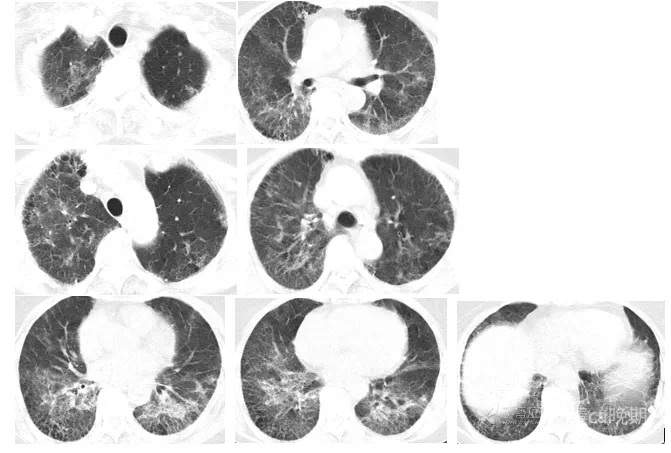

2023年2月10日PET-CT: 1.全身PET-CT扫描未见确切恶性肿瘤征象。2.双肺胸膜下网格状改变,双肺多发斑片状密度增高影并代谢增高,考虑为双肺间质性炎。3.右肺上叶及左肺下叶小结节,代谢未见增高,考虑为慢性炎性结节。双肺上中叶及左肺下叶钙化灶。4.纵隔1R/L、2R/L、4R/L、7、10R稍大淋巴结,部分密度稍高,放射性摄取增高,SUVmax约为5.8,考虑为慢性炎性淋巴结。5. 胃窦壁增厚,放射性摄取增高,SUVmax约为3.3 ,考虑炎性病变或生理性摄取。6.双侧臀部皮下脂肪间隙内絮状密度影并代谢增高,右侧肩关节周围组织代谢增高,考虑为炎性病变。7.右前臂局灶性放射性摄取浓聚,考虑为放射性药物沾染。

胸部CT复查(2023-2-16):双肺见散在斑片状、片状、条索状密度增高影,双肺胸膜下及双肺下叶肺组织呈网格状改变,多考虑肺间质纤维化并炎症,对比前片局部斑片影较前稍减少。